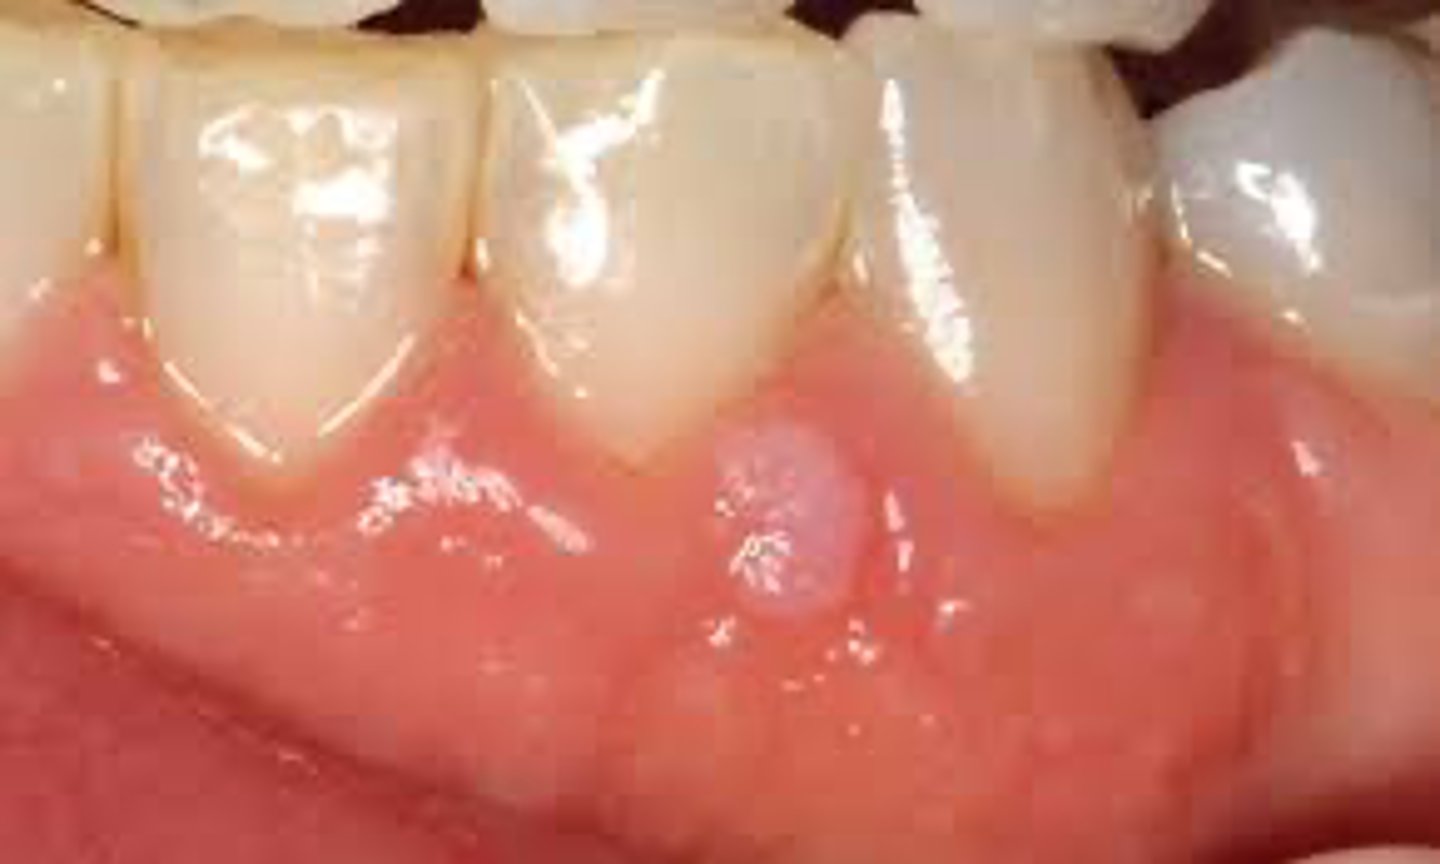

A patient presents with multiple pinpoint red spots (<2 mm) on the soft palate.

What is the most likely diagnosis?

petechiae